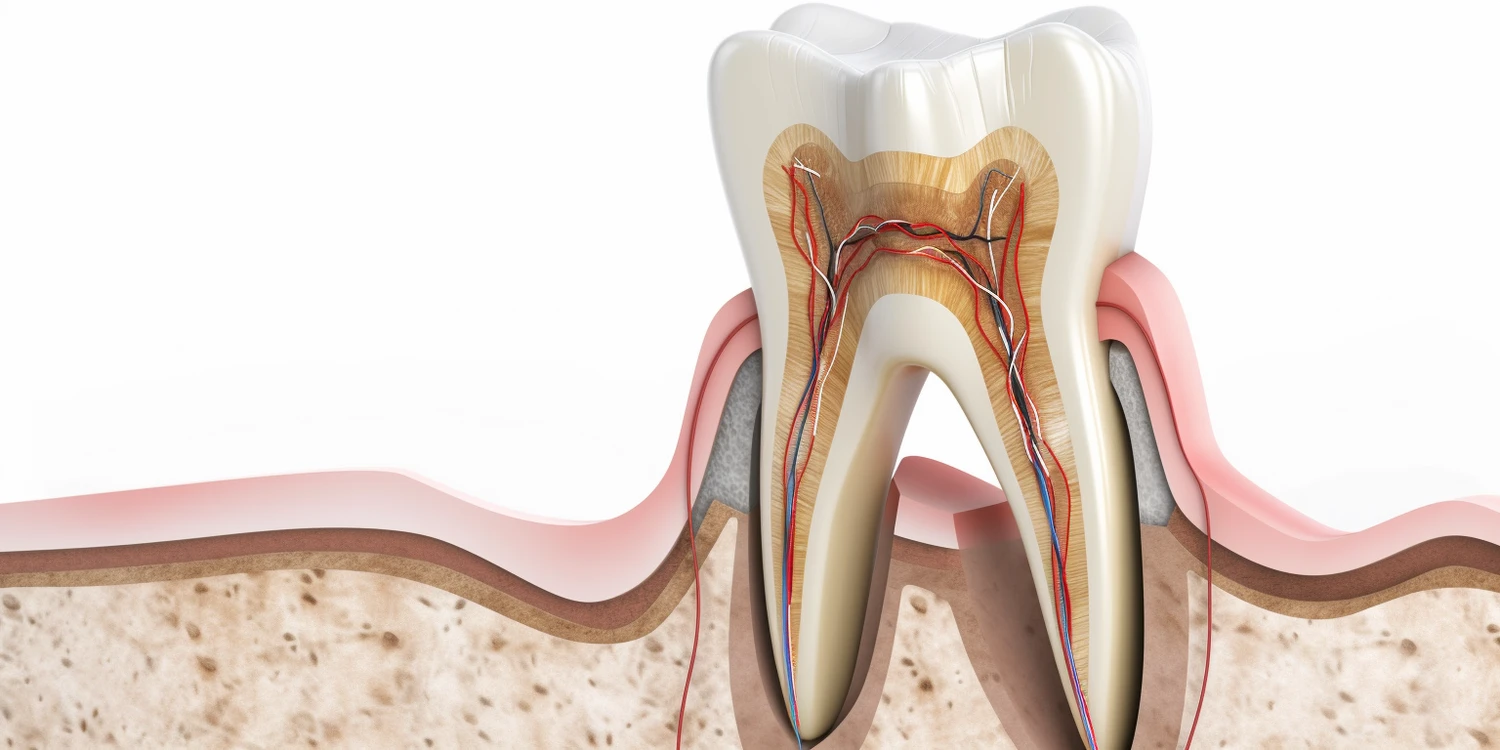

Wizyta u dentysty to nie tylko czas na leczenie problemów stomatologicznych, ale także okazja do oceny ogólnego stanu zdrowia zębów i dziąseł. Podczas pierwszej wizyty specjalista przeprowadza dokładny wywiad medyczny oraz analizuje historię stomatologiczną pacjenta. Następnie przystępuje do badania klinicznego, które obejmuje ocenę stanu zębów pod kątem próchnicy, uszkodzeń czy przebarwień. Dentysta zwraca uwagę na kondycję dziąseł oraz ich reakcję na bodźce mechaniczne. Często wykonuje również zdjęcia rentgenowskie, które pozwalają na dokładną ocenę stanu korzeni zębów oraz kości szczęki. Dzięki tym informacjom dentysta może postawić diagnozę oraz zaproponować odpowiednie leczenie lub profilaktykę. Ważne jest, aby pacjent był otwarty na wszelkie sugestie specjalisty i zadawał pytania dotyczące swojego stanu zdrowia.